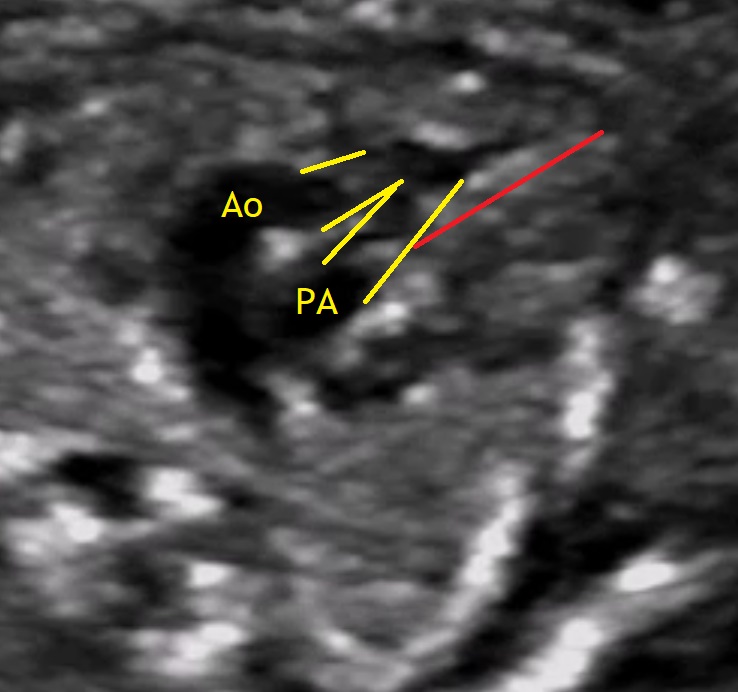

One out of 10.000 children is born with a double outlet right ventricle (DORV), which means both great vessels arise either entirely or predominantly from the right ventricle. The aorta can be found in right anterior (D-transposition type DORV), right posterior (tetralogy of Fallot type DORV), right lateral (side by side) or left anterior position (L-transposition type DORV). Commonly there is also a ventricular septal defect (VSD) which can be subaortic, subpulmonary, subaortic and subpulmonary (doubly commited) and remote (nonrelated to both arteries) (Abuhamad A., Chaoui R., 2010).

Our featured video shows a case of DORV diagnosed in the 19th week of pregnancy. The image below shows the pathological doppler findings of the ductus venosus.